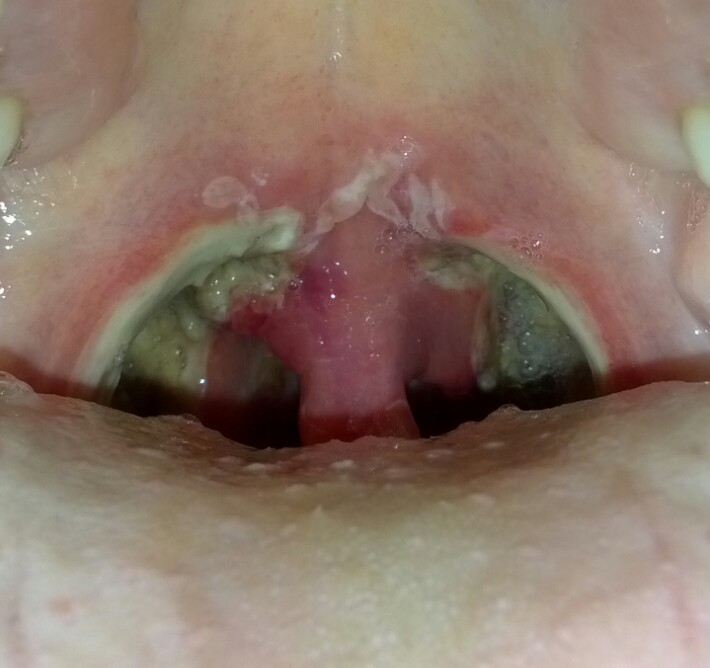

편도염 환자는 일반적으로 인후통, 삼킴 곤란, 불쾌감, 발열을 겪는다.[5][14][16] 환자의 편도와 목 뒤쪽은 홍반이 나타나고 부어오르며, 때로는 흰색 삼출물(고름)을 내기도 한다.[5][16][15] 일부 환자는 목 림프절에 압통성 부종(누르면 아픈 부기)을 보이기도 한다.[5][16]

바이러스성 편도염은 기침, 콧물, 쉰 목소리, 입이나 목의 물집을 유발하기도 한다.[17] 전염성 단핵구증은 붉은 점상 출혈 또는 혀까지 번질 수 있는 흰색 삼출물과 함께 편도를 붓게 할 수 있으며, 발열, 인후통, 경부 림프절 부종, 간 및 비장 비대와 동반될 수 있다.[18] 세균성 편도염은 "성홍열양" 발진, 구토, 편도 반점 또는 삼출물을 유발할 수 있다.[5][17]

주요 증상으로는 38도 이상의 발열, 인두 통증, 오한, 전율, 권태감, 두통, 관절통 외에도, 턱 아래나 경부의 림프절 부종 등이 있으며, 통증이 귀나 측두부로 확산되기도 한다.[52][53] 고열을 동반하는 경우가 많아, 고열에 특징적인 증상이 나타난다. 편도염은 감기에서 비롯되기도 하며, 편도염이 원인이 되어 코나 후두, 기관 등에 염증이 생겨 결과적으로 감기 증상이 나타나기도 한다. 따라서 편도가 붓는 경향이 있는 사람은 감기에 잘 걸리거나 감기에 걸리면 바로 인두가 붓는다고 여겨지는 경우가 많다. 관절통이 나타나기도 하며, 감기에 이어 나타나는 경우가 많다. 농전이 퍼져 편도 표면에 있는 음와를 흰 막으로 덮게 되는데, 이를 음와성 편도염이라고 한다. 원인으로는 용혈성 연쇄상구균, 포도상구균, 폐렴구균 등이 있다. 그러나 사전에 감기에 걸린 단계에서 항생제를 사용하면 원인을 특정할 수 없는 경우도 많다.[53]